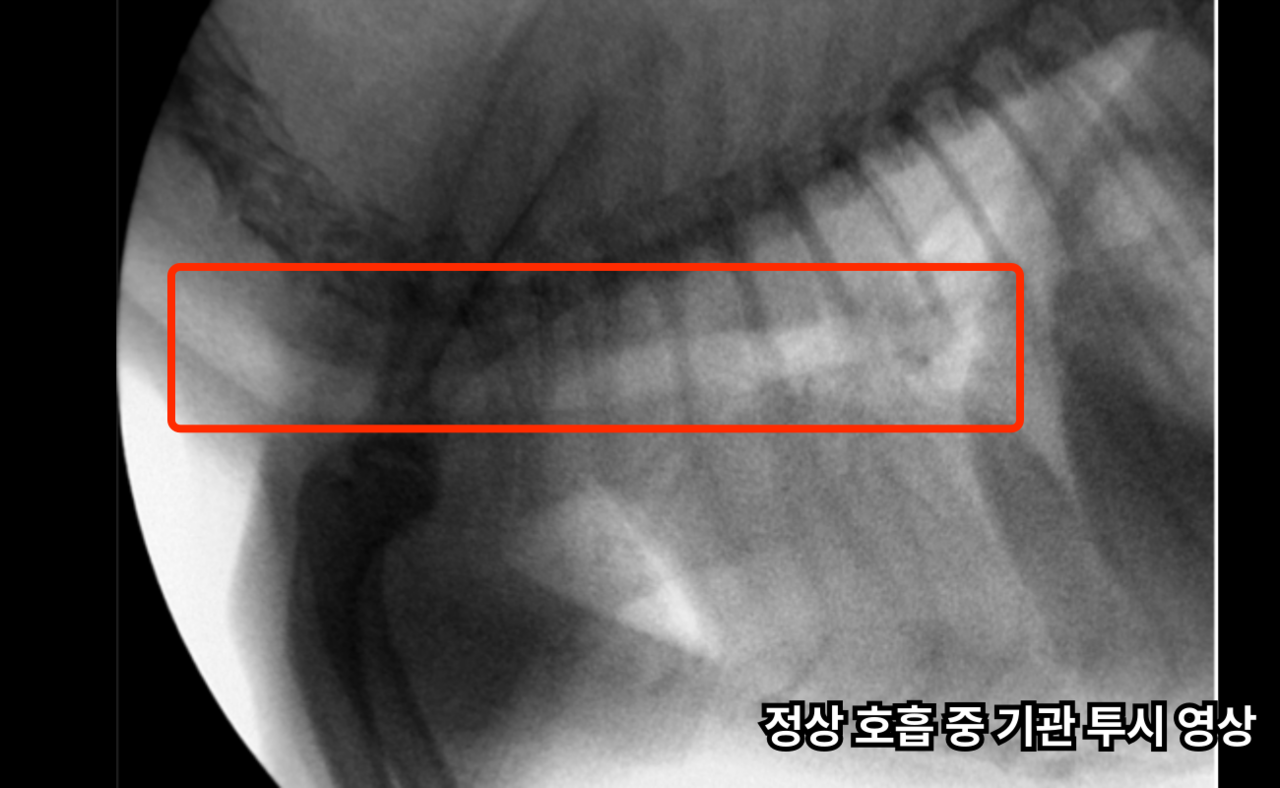

비전플로우는 실시간 투시 영상을 통해

숨쉴 때의 기관의 구조와 변화를 평가합니다.

Fluoroscopic examination of the trachea

숨을 쉴 때 공기가 지나가는 통로(기관)이 좁아지면, 강아지가 숨쉬기 힘들어지거나 기침, 쌕쌕거림, 호흡 곤란 같은 증상이 생길 수 있습니다.

VisionFlow는 Oscar Prime C-arm 장비를 이용한 실시간 X-ray 영상 검사입니다.

기관의 움직임 평가

비전플로우 검사를 통해 실시간 촬영을 진행하여 숨을 들이마실 때, 내쉴 때 기관이 눌리거나 좁아지는 지 실시간으로 확인합니다.